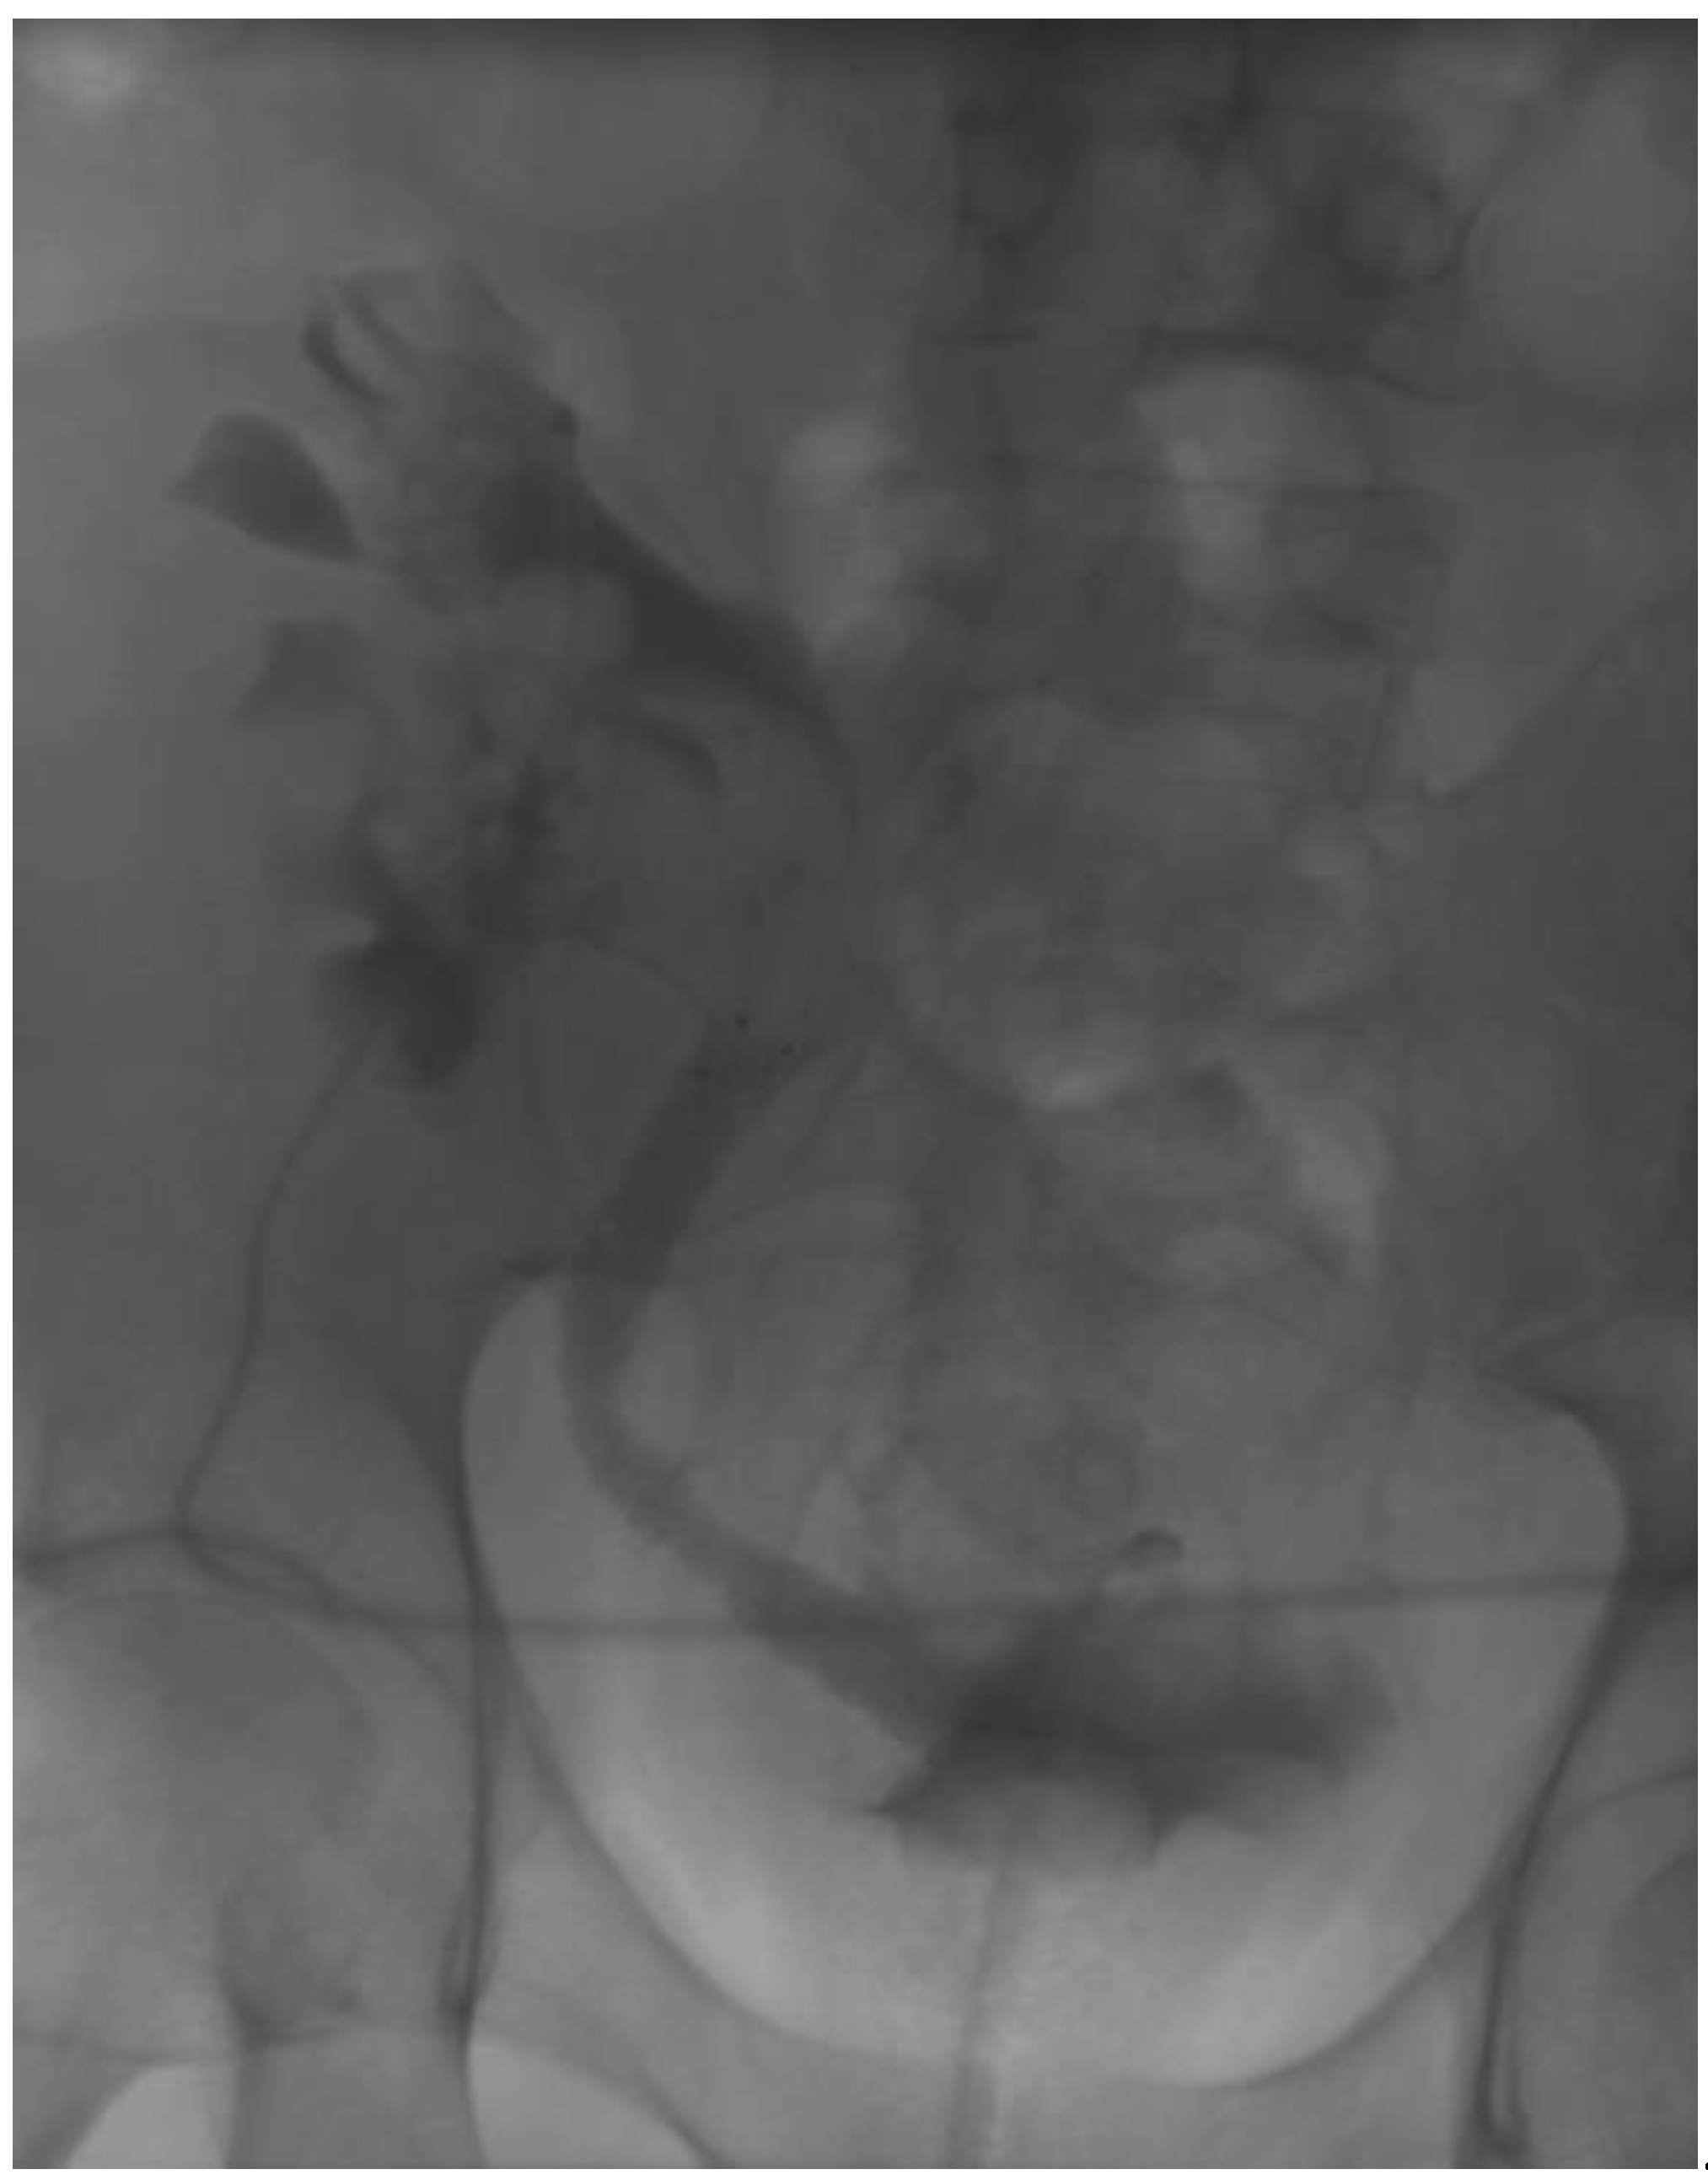

2. Materials and Methods

3. Results